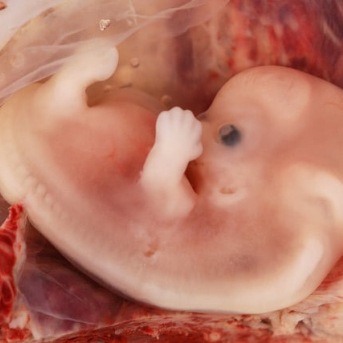

Assim que o óvulo é fecundado pelo espermatozoide, começa ali a formação de uma nova vida. Junto com essa nova condição, vários outros órgãos provisórios também começam a se formar e um deles é a vesícula vitelina ou vitelínica. A vesícula vitelina é... Continuar LendoAssim que o óvulo é fecundado pelo... Continuar Lendo